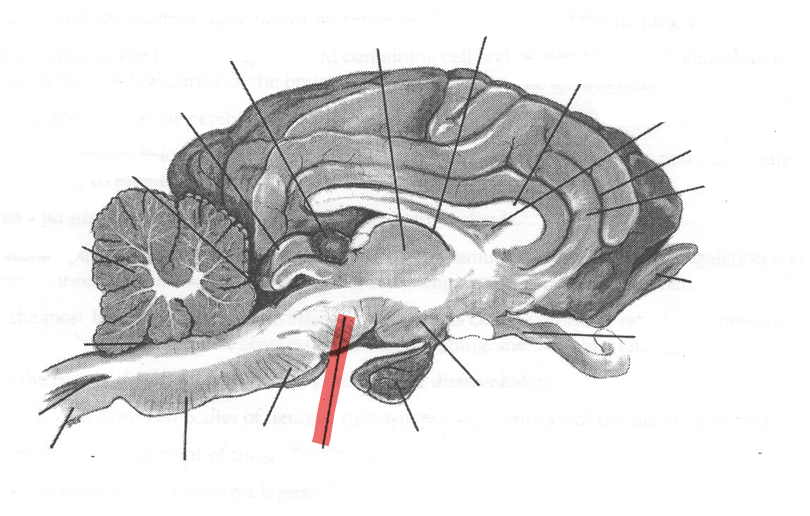

Identify highlighted arrow

Midbrain